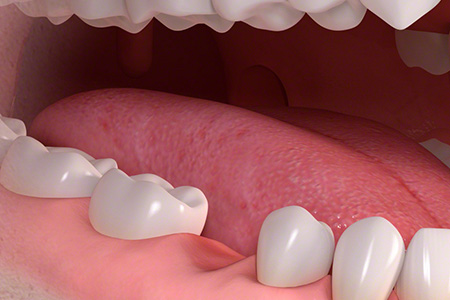

インプラントは、失った歯の部分の骨にチタン製のネジを植え込み、その上に歯の被せ物を乗せる構造をしています。

インプラントの一番の特徴は、入れ歯やブリッジと違い他の歯に迷惑をかけないところです。入れ歯の様に健康な歯にフックをかけたり、ブリッジの様に前後の歯を削らなくて済むので長い目で見ると一番周りの歯に優しく、長持ちすることが論文でも証明されています。 また、本来の歯の形と同じ形状大きさをしているので、異物感もなく自分の歯の様に噛むことが可能です。 |